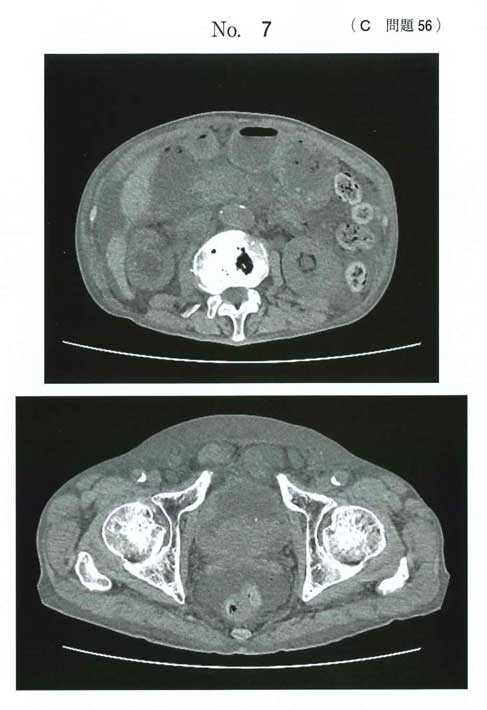

CTで両側水腎症、膀胱腫瘍を認めます。

膀胱癌による両側上部尿路閉塞からの急性腎後性腎障害です。

下部尿路閉塞ではないので、c.尿道カテーテル留置は無効です。腫瘍への機械的刺激により血尿を再燃させるリスクがあります。

d.膀胱瘻は腫瘍を穿刺し得るため禁忌です。

CT所見:膀胱腫瘍と両側水腎症が認められる。

膀胱癌に伴う両側尿管閉塞による急性腎不全(腎後性)と考えられる。このため膀胱へのアプローチは無意味である。腎瘻造設を行う。

なおCT所見としては、腹水・皮下や後腹膜の浮腫・宿便もみられます。